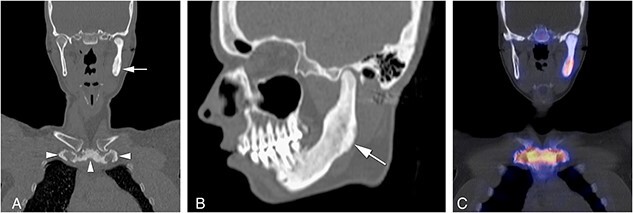

Osteitis of the sternocostoclavicular (SCC) region, referred to as sternocostoclavicular hyperostosis (SCCH), is the clinical expression of chronic non-bacterial osteitis (CNO) in adults with this rare chronic auto-inflammatory disorder of the axial skeleton. The diagnosis is based on distinctive computerized tomography (CT) features of sclerosis and hyperostosis of the SCC region, and local increases in osteoid formation visualized by high radiopharmacon uptake on skeletal scintigraphy but clear radiologic diagnostic criteria are lacking. In a cross-sectional study, CT scans and whole-body skeletal scintigraphy images obtained in 169 patients seen at the Center for Bone Quality of the Leiden University Medical Center between 2008 and 2018 with a suspected diagnosis of CNO of the SCC region were re-evaluated by 2 skeletal radiologists and 2 nuclear physicians. The diagnosis was confirmed in 118 (70%) predominantly female patients (n = 103, 89.2%); median age at first symptoms 45 years (range 20-73). The diagnosis was excluded in the remaining 51 "non-CNO" patients. Increased radiopharmacon uptake at the SCC region was observed in 82% CNO patients, with the manubrium sterni having the highest predictive ability to discriminate on both imaging modalities. The prevalence of sclerosis of the clavicles, manubrium and first ribs was significantly higher in CNO patients (P < 0.001). Hyperostosis was not observed in non-CNO patients. 46 CNO versus only 2 non-CNO patients had costoclavicular ligament calcification. Our findings identify CT scan features of sclerosis and hyperostosis of manubrium sterni, medial end of clavicles and first ribs, and calcification of costoclavicular ligaments, associated with increased tracer uptake on skeletal scintigraphy at the SCC region, specifically manubrium sterni, as well-defined imaging diagnostic criteria for adult CNO. Pitfalls encountered in the diagnosis of CNO are highlighted. These defined imaging diagnostic criteria for adult CNO should facilitate the diagnosis of this rare auto-inflammatory bone disease across the spectrum of its early to late stages.

Abstract Image